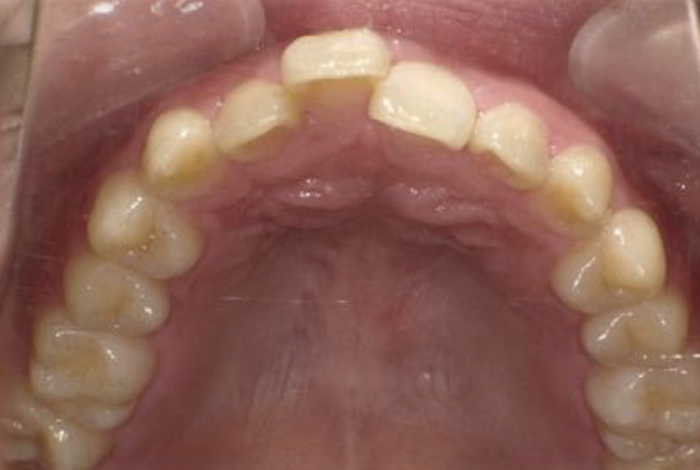

| 矯正装置装着時 | |

![]() |

| 年齢/性別 | 24歳/男性 |

| 治療内容 | 上の前歯が出っ張りによって隙間が出来ているため、両方を改善したいと来院されました。上の歯のみに全体に装置を付けて治療をすることになりました。 |

| 治療期間 | 装置装着期間は、10か月です。その後安定させるための保定装置を1年半ほど使用して頂きました。 |

| 治療上でのリスク | 歯の移動により歯根が吸収され短くなる可能性があります。歯の動き具合には個人差があります。衛生面が不良となりコンディションを損ねる可能性があります。 |

| 治療費 (全て税抜き) |

検査・診断 ¥25,000 |

| 装置代 ¥300,000 | |

| 毎月1度の調節料 ¥6,500 | |

| 保定観察料 ¥5,000 |